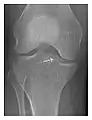

High-energy trauma fractures

Occult osseous injuries may result from a direct blow to the bone by compressive forces of adjacent bones against one another or by traction forces during an avulsion injury. Lesions in the tibial plateau, hip, ankle, and wrist are often missed. In a tibial plateau fracture, any disruption of the posterior and anterior cortical rims of the plateau should be sought. Impaction of subchondral bone will appear as an increased sclerosis of the subchondral bone (Figure 1). In the hip, posterior acetabular fractures also present subtle radiographic findings. The acetabular lines should then be carefully examined keeping in mind that the posterior rim, which is harder to see on X-rays, is more frequently fractured than the anterior rim (Figure 2). In the wrist, detection of carpal bone fractures is often challenging, with up to 18% of scaphoid fractures radiographically occult. Carpal fractures, especially the scaphoid, are associated with the risk of avascular necrosis. In apparently normal wrist radiographs from symptomatic patients, if there is history of a fall on an outstretched hand with pain in the anatomic snuffbox, suggesting scaphoid injury, the initial examination with posteroanterior, lateral, and pronation oblique views must be complemented by other specific views such as supination oblique and the "scaphoid" view A careful examination of cortices for evidence of discontinuity or offset and cancellous bone for lucency is necessary (Figure 3).[1]

Figure 1: A 56-year-old woman presenting with left knee pain after a fall. (a) Initial anteroposterior radiograph was considered normal, however, subtle cortical disruption of the anterior rim of the medial tibial plateau, medial to the tibial spine, is noted (arrow). (b) Coronal T1-weighted MRI confirms the cortical disruption (arrow) and shows extensive fracture through the proximal tibia. (c) Coronal proton density-weighted image with fat saturation shows extensive edema in the subchondral bone. Note also hypersignal adjacent to the medial collateral ligament corresponding to a grade I sprain (arrowheads).[1]